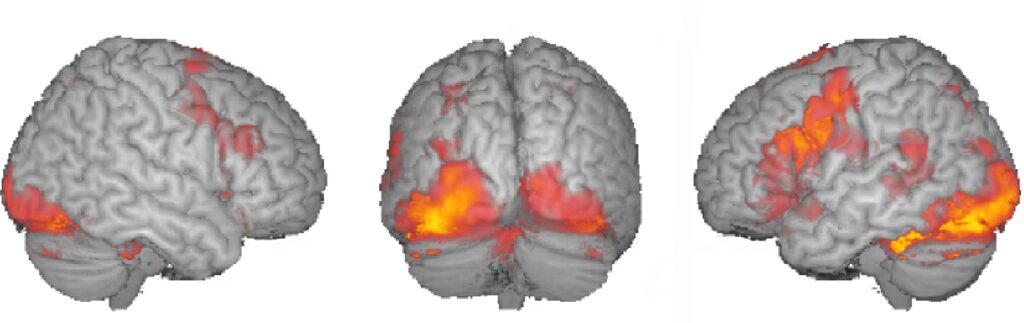

La estadística se aplica a nivel de vóxel (el equivalente tridimensional de un píxel en las imágenes de MRI). Se compara la señal de cada vóxel a lo largo del tiempo en las diferentes condiciones para identificar aquellos que muestran un cambio significativo y sincronizado con la tarea o estímulo. El resultado es un mapa estadístico paramétrico que muestra las regiones "activadas". Sin embargo, la interpretación estadística es compleja, especialmente debido a las múltiples comparaciones simultáneas (miles de vóxeles) y la presencia de ruido no relacionado con la tarea (movimiento del sujeto, respiración, pulsaciones cardíacas).

- Planificación Neuroquirúrgica: Una de las aplicaciones clínicas más importantes es el mapeo funcional prequirúrgico. Antes de una cirugía cerebral (por ejemplo, para tumores o epilepsia), es crucial identificar la ubicación exacta de áreas cerebrales críticas, como las relacionadas con el lenguaje, la vista, el oído y el movimiento, para evitar dañarlas durante el procedimiento. La fMRI permite realizar este mapeo de forma no invasiva, presentando al paciente tareas sencillas (mover los dedos, escuchar sonidos, ver imágenes, nombrar objetos) dentro del escáner. Los resultados se pueden integrar con sistemas de navegación quirúrgica. Esto ofrece una alternativa menos invasiva que pruebas como el test de Wada para determinar la dominancia hemisférica del lenguaje.

- Estudio de Trastornos Psiquiátricos: Se emplea para investigar las bases neuronales de condiciones como la depresión, la ansiedad, la esquizofrenia o el trastorno bipolar. Mediante tareas diseñadas para activar procesos cognitivos o emocionales específicos, la fMRI puede revelar patrones de actividad o conectividad atípicos asociados a estas enfermedades. Por ejemplo, estudios con el test de Stroop han mostrado diferencias en los patrones de activación en pacientes con depresión o ludopatía.

- Neurodesarrollo y Trastornos Infantiles: Dada su naturaleza no invasiva, la fMRI es valiosa para estudiar el desarrollo cerebral normal y atípico en niños. Se ha utilizado para investigar trastornos como el autismo (mostrando diferencias en el procesamiento de caras) o la dislexia del desarrollo (identificando déficits en circuitos posteriores implicados en la lectura). También puede monitorizar la respuesta a intervenciones educativas o terapéuticas.